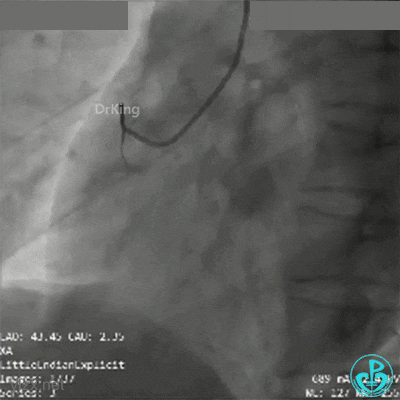

球囊再次扩张远端后,替罗非班注射,示远端狭窄改善,近端出现什么情况?血栓?夹层?

直接指引导管抽吸,未见血栓。

冒烟显示近端仍然有异物,远端造影剂滞留。

高度怀疑近端夹层。